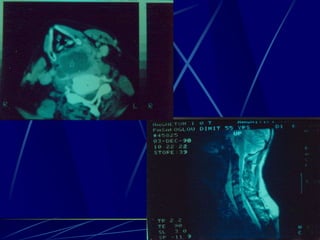

Φυματίωση της σπονδυλικής στήλης